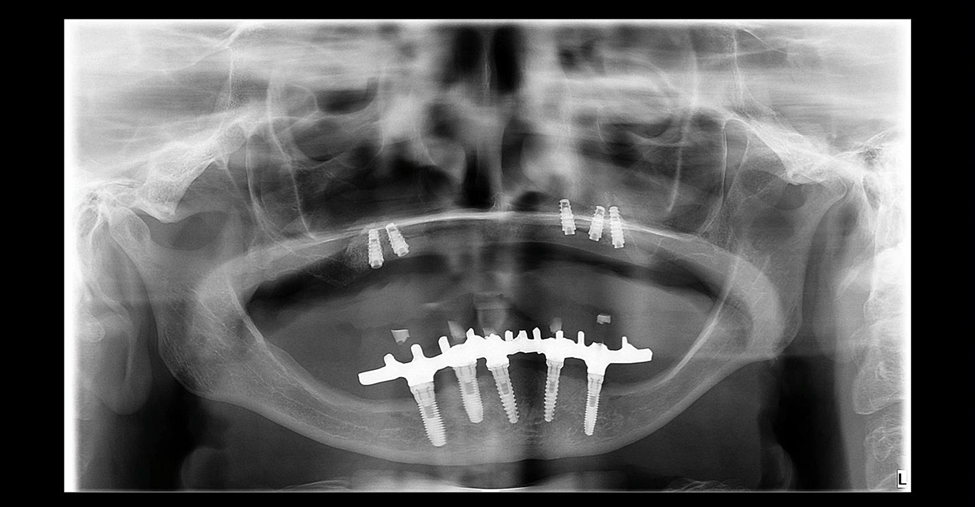

Realizamos a cirurgia de instalação dos implantes (Maestro CM, Implacil De Bortoli) sob sedação endovenosa e monitoramento por médica anestesista em nosso consultório cirúrgico. A radiografia panorâmica pós-operatória mostra a distribuição dos implantes (Foto 5). A prótese total da paciente foi aliviada internamente e reembasada com material macio (COE-SOFT) para que pudesse ser utilizada durante o tempo de Osseointegração dos implantes (seis meses).

A cirurgia de reabertura dos implantes foi realizada com instalação simultânea dos componentes protéticos e moldagem para dar início ao processo de confecção da prótese protocolo. A variedade de componentes protéticos disponíveis na Implacil De Bortoli foi primordial nesse caso, onde, devido à proximidade dos implantes do lado esquerdo e visando facilitar a higienização da área e reduzir as chances de um processo de peri-implantite, utilizamos um componente mini cônico angulado e um componente micro cônico reto nos implantes das regiões de 23 e 24, respectivamente. O uso destes componentes possibilitou um bom eixo de saída dos parafusos protéticos e a manutenção de espaço entre eles. A radiografia panorâmica final e as fotos clínicas apresentam a finalização do caso com a reabilitação protética (Fotos 6, 7 e 8).